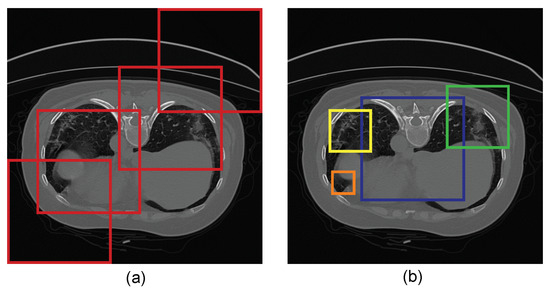

2.3. Architecture of LungINFseg

3.3. Analysis of the Performance of the Proposed Model